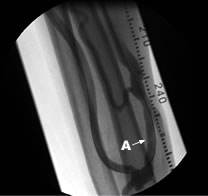

Aシャント感染部位から膿が出ています。 Bシャント感染部位の人工血管が露出しています。

シャントや動脈表在化、透析用カテーテルでは、細菌により感染することがあり、その病態に応じた治療が必要となります。自己静脈シャントでは感染部位を切除して新たなシャントを作製しますが、人工血管シャントでは人工血管全体を完全に摘出する必要がある場合が多く、次のシャント作製を含めると治療に必要な期間が長くなる傾向にあります。表在化動脈への感染では、単純に動脈を取り去ることが出来ない場合、バイパス術を必要とします。カテーテル感染は出口部感染だけであれば局所治療で済みますが、カテーテル感染であれば入れ替えが必要です。